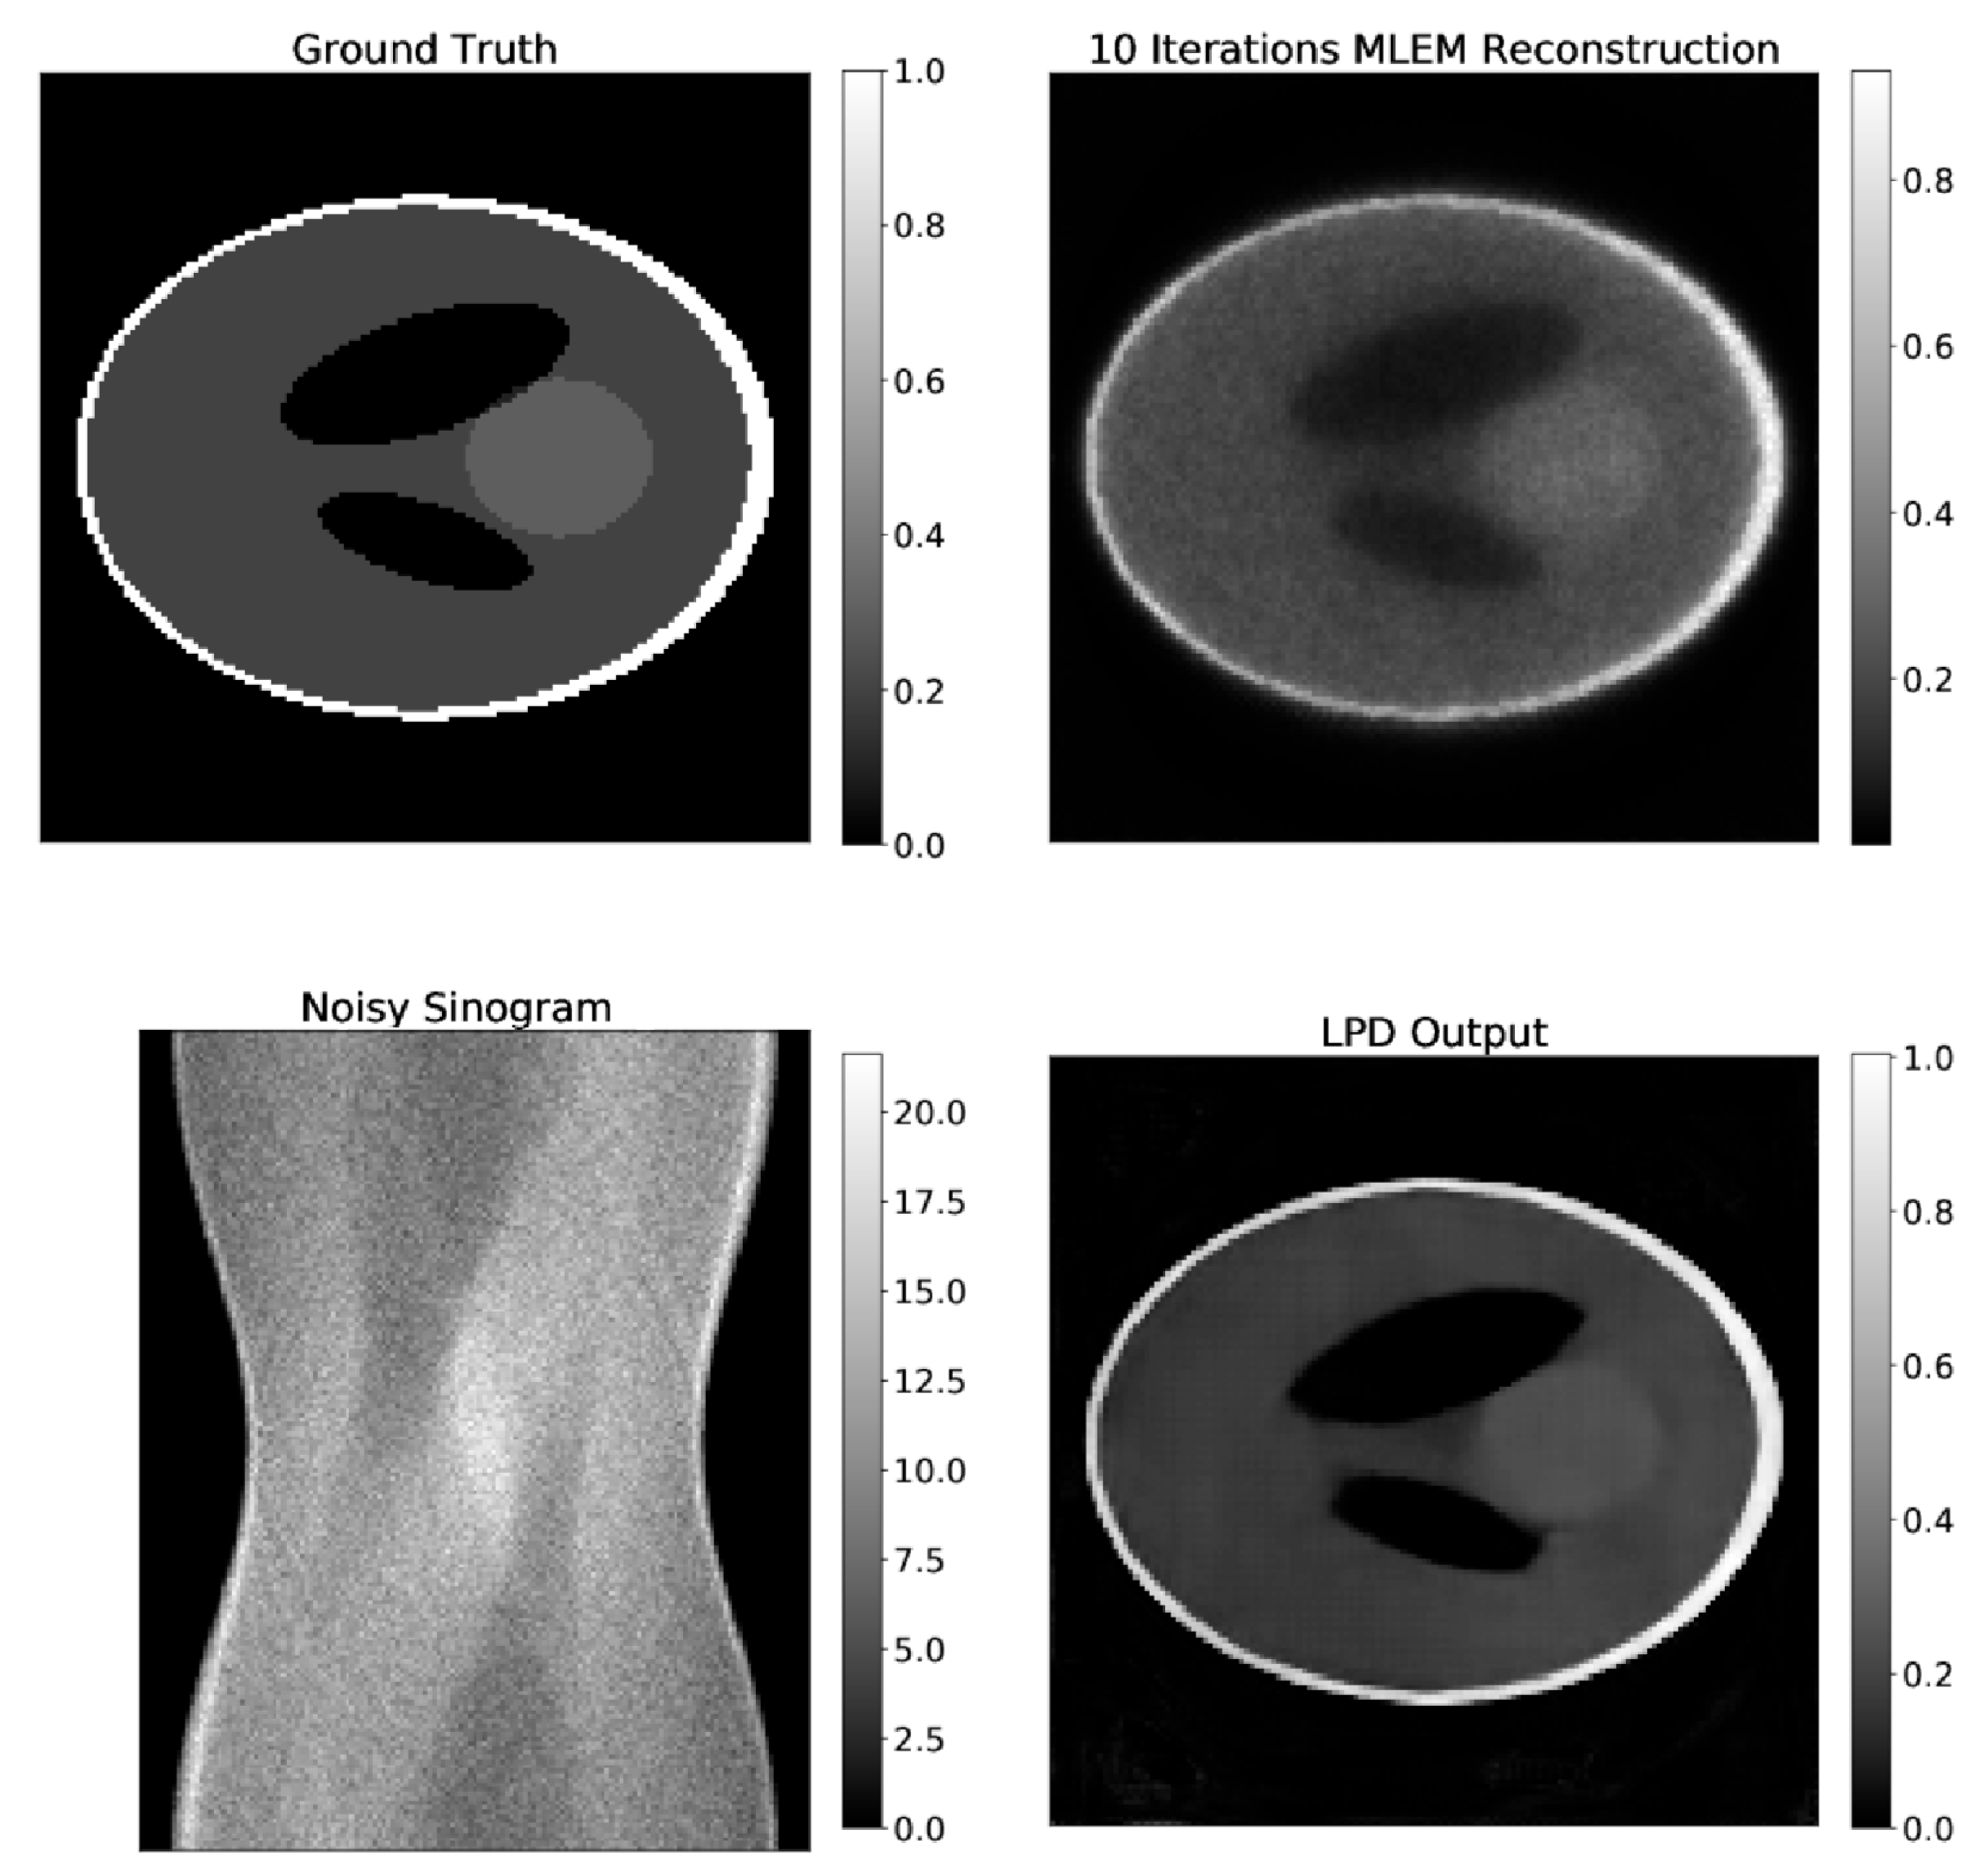

3.1. Results on Synthetic Data